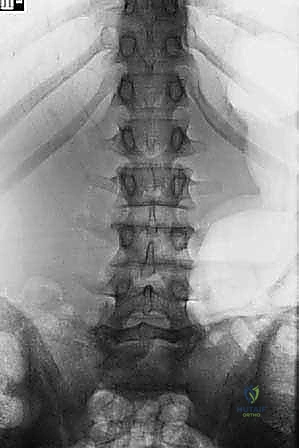

تبدأ رحلة الشفاء في عيادة الدكتور هطيف بتشخيص دقيق وشامل. الانزلاق عالي الدرجة يتطلب تصويراً متقدماً لتحديد زاوية الانزلاق، مقدار الضغط العصبي، وجودة العظام.

- الأشعة السينية الديناميكية (Dynamic X-rays): صور في وضعية الانحناء للأمام والخلف لتقييم مدى عدم استقرار الفقرات وحركتها غير الطبيعية.

- التصوير بالرنين المغناطيسي (MRI): هو المعيار الذهبي لرؤية الأنسجة الرخوة. يوضح بدقة متناهية حالة الأقراص الغضروفية، ومقدار الاختناق في القناة الشوكية، والضغط الواقع على جذور الأعصاب.

- التصوير المقطعي المحوسب (CT Scan): يقدم تفاصيل دقيقة للبنية العظمية، وهو ضروري جداً للتخطيط الجراحي وتحديد مسار المسامير (Pedicle Screws) في الجراحة.

- التخطيط الكهربائي للعضلات والأعصاب (EMG): لتقييم مدى الضرر الذي لحق بالأعصاب الطرفية وتحديد ما إذا كان قابلاً للعكس.